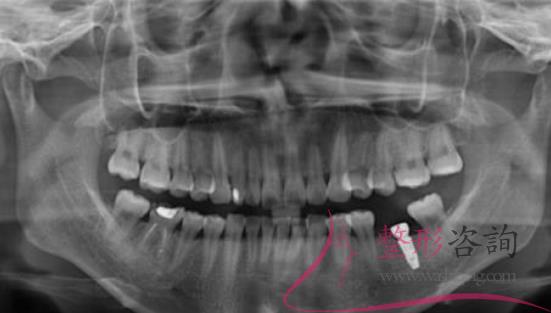

聽說深圳種植牙齒比較好,爸爸的牙齒少了很多,如果不及時(shí)的去補(bǔ)充就會(huì)影響到周圍的牙齒,假牙不方便,而且也不能咬硬的東西,所以決定去深圳種植牙齒,聽說種植牙齒和真的牙齒一樣,隨便用,不會(huì)對(duì)人們?cè)斐捎绊懀?jīng)過仔細(xì)的了解到深圳種植牙的價(jià)格后,帶爸爸去正夫口腔醫(yī)院做了種植牙。

通過各種了解后,最后決定帶著爸爸來到了深圳正夫口腔醫(yī)院種植牙齒,來到醫(yī)院后,醫(yī)生仔細(xì)檢查了爸爸的身體,經(jīng)過仔細(xì)的確認(rèn)爸爸的身體沒有任何的異常情況,醫(yī)生才選擇了手術(shù),手術(shù)前爸爸有一些緊張,但是醫(yī)生耐心的溝通,徹底的消除了爸爸的緊張感,就著手準(zhǔn)備手術(shù)了,差不多經(jīng)過3個(gè)左右的時(shí)間,手術(shù)結(jié)束了。

爸爸說,這次手術(shù)并沒有疼痛感出現(xiàn),整個(gè)手術(shù)都非常的輕松,剛種植完牙齒后會(huì)有一些不適應(yīng),可能是麻藥的緣故,醫(yī)生說麻藥藥效散去后會(huì)有一些疼痛感出現(xiàn),爸爸說是有一些疼痛感,但是并不是非常明顯,這種疼痛也是可以忍受的。

距離種植牙齒已經(jīng)有半年左右的時(shí)間了,爸爸說已經(jīng)適應(yīng)了這種情況,一切都非常的好,牙齒也可以咬各種東西,現(xiàn)在爸爸再也不會(huì)擔(dān)心這種食物不能吃,那種食物不能吃了,全部都可以吃了,硬的食物,酸的食物,甜的食物都不會(huì)再引起牙痛了,這次種植牙齒真的非常滿意。